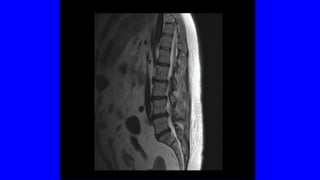

• ENCUESTA DE SALUD DEL INE: LA PREVALENCIA DEL DOLOR LUMBAR Y/O

CERVICAL EN ESPAÑA ES DEL 25% (> 10 MILLONES)

• PRIMER MOTIVODE CONSULTA MÉDICA • < 45 AÑOS ES EL PRIMER PROBLEMA INCAPACITANTE • EN EEUU ES EL MAYOR GASTO EN SALUD (IT, ANALÍTICAS, RX,RNM) • IMPLICA SUFRIMIENTO, DIFICULTAD PARA EL DESCANSO, TRISTEZA Y AL FINAL DEPRESIÓN: COMPONENTE PSICOSOCIAL • ENCUESTA DE SALUD DEL INE: LA PREVALENCIA DEL DOLOR LUMBAR Y/O CERVICAL EN ESPAÑA ES DEL 25% (> 10 MILLONES)